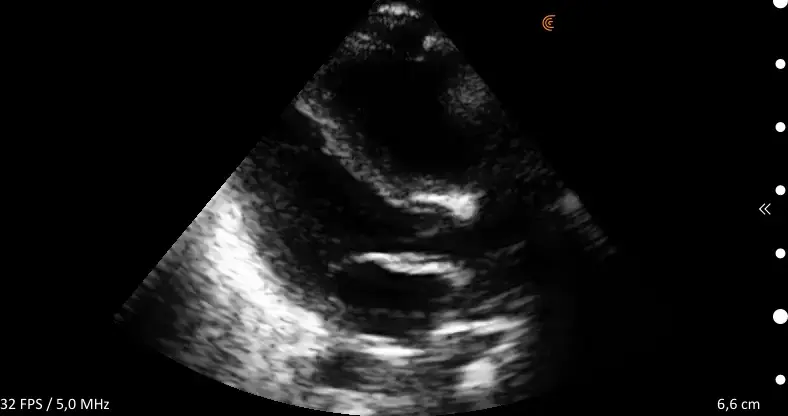

ProbeFix Dynamic is a new device that enables high-quality ultrasound measurements during dynamic exercise by keeping an ultrasound probe in place, allowing for muscle monitoring during intense movement and creating new research possibilities in muscle imaging.